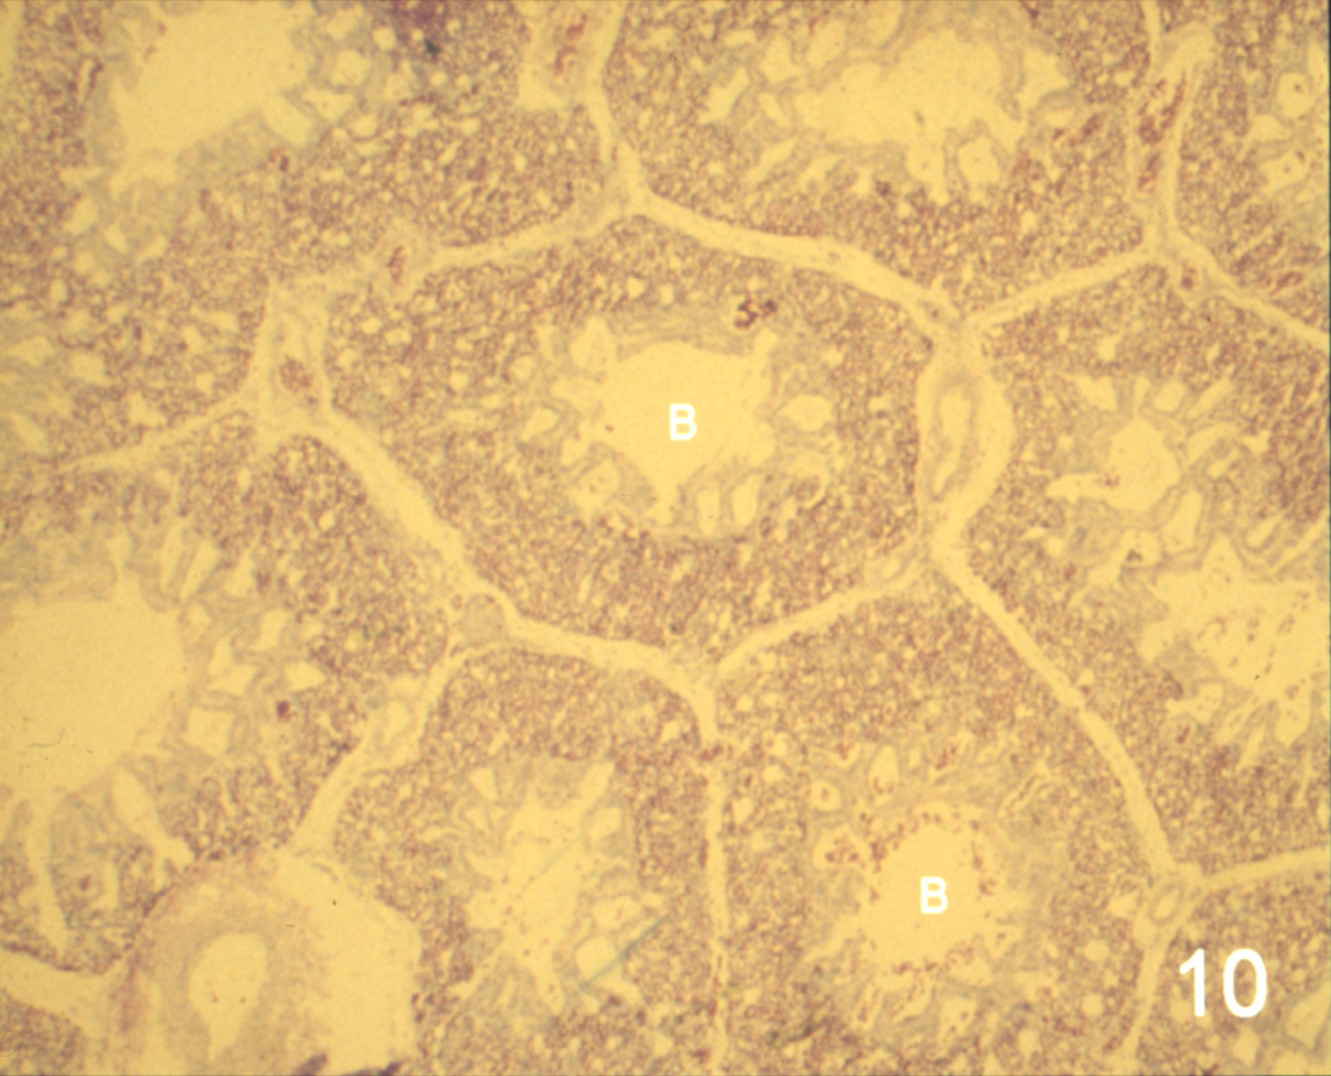

Ascites syndrome in meat-type chickens (slide study set no. 23)

Chickens--Diseases Ascites

Slide Study Set #23, Ascites Syndrome in Meat-Type Chickens (includes 27 color slides), 2001